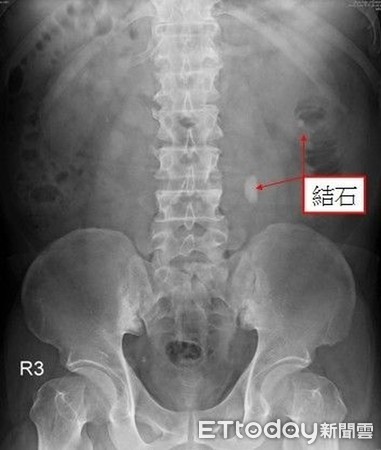

▲患者尿道內有多顆結石。(圖/安南醫院提供)

台灣民眾嗜手搖飲料,學生族群更是人手每天一杯,更甚者將手搖飲替代開水度日;一名男大生因腹痛就醫,經檢查發現泌尿道「結石纍纍」,問診時表示自己每天喝至少3杯手搖飲,經醫師治療並服用藥物後,已順利將體內6顆0.5公分大小的石頭排出。